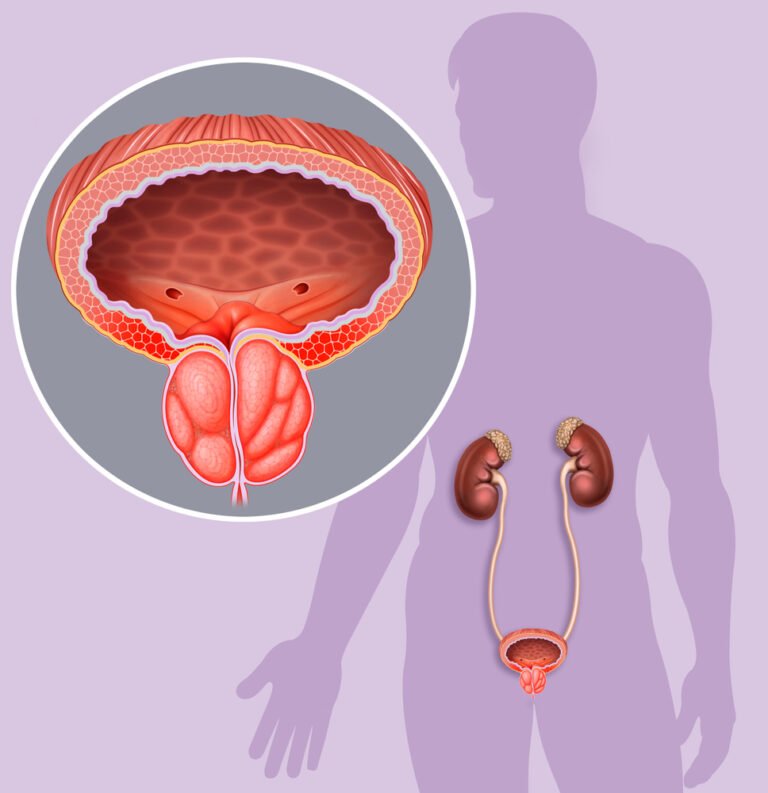

Dampak Buruk dan Bahaya Radang Prostat yang Menyebar ke Ginjal

Infeksi yang menetap pada area prostat mampu menjalar menuju organ ginjal melalui saluran kemih. Fenomena ini seringkali mengakibatkan kerusakan jaringan ginjal yang bersifat menetap dan membahayakan kesehatan tubuh.

Selanjutnya bakteri penyebab infeksi dapat memicu kegagalan fungsi organ vital tersebut secara tiba-tiba. Pasien memerlukan tindakan medis intensif guna mencegah penyebaran racun ke seluruh aliran darah tubuh.

Sistem imun tubuh biasanya bekerja ekstra keras untuk melawan serangan bakteri yang sangat agresif. Pasien sebaiknya mewaspadai munculnya rasa nyeri yang menjalar hingga ke area punggung bawah.

Oleh karena itu penderita harus segera melakukan pemeriksaan laboratorium untuk memantau aktivitas bakteri yang menyerang. Kondisi tersebut menuntut kewaspadaan tinggi agar fungsi filtrasi darah tetap berjalan secara optimal harian.

Risiko Retensi Urin Akut Mengenali Bahaya Radang Prostat Sejak Dini

Pembengkakan kelenjar yang membengkak menekan saluran uretra sehingga menghambat aliran pembuangan air seni harian. Akibatnya kandung kemih tidak mampu mengosongkan diri sepenuhnya meski penderita sudah berusaha mengejan kuat.

Kekuatan pancaran urin akan melemah secara signifikan seiring dengan bertambahnya tingkat keparahan infeksi tersebut. Kandung kemih yang terus merenggang akibat tekanan urin berlebih dapat memicu kerusakan syaraf.

Pasien yang mengalami retensi urin akut seringkali merasakan tekanan perut bawah yang sangat menyesakkan. Pasalnya penumpukan urin yang berlebihan di dalam kandung kemih memicu rasa tidak nyaman kronis.

Kondisi darurat ini membutuhkan bantuan pemasangan kateter untuk membantu mengeluarkan cairan sisa metabolisme tubuh. Hasilnya penderita terhindar dari risiko pecahnya dinding kandung kemih akibat tekanan cairan yang tinggi.

Penyumbatan yang terjadi secara terus-menerus dapat melemahkan otot-otot saluran kemih secara permanen dan merugikan. Kondisi uretra yang terjepit memerlukan tindakan medis segera agar aliran pembuangan kembali berjalan lancar.